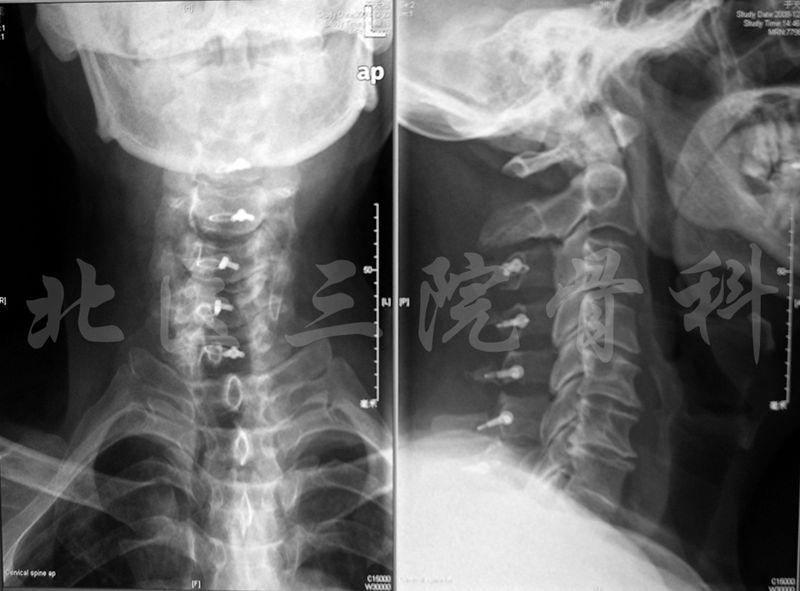

X线片

术后X线